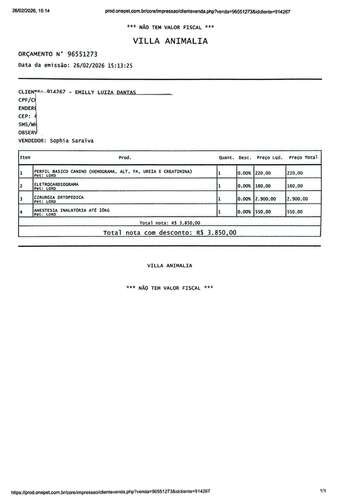

Oi aumigos, meu nome é Lord, tenho 9 anos e sou o amor da vida das minhas mães e a alegria de todos que convivem comigo. Fui atropelado e fraturei o final da minha coluna (vértebras sacrais), prejudicando minha patinha e meu rabinho, estou sentindo muita dor e preciso de cirurgia o mais rápido possível 😢. Como foi um acidente, pegou minhas mamães desprevenidas, peço ajuda de vocês, para que eu possa ficar curado e voltar a correr e brincar 🐶

Obs.: Os valores que estamos pedindo é para custear a cirurgia, o pós cirúrgico e os gastos adicionais.